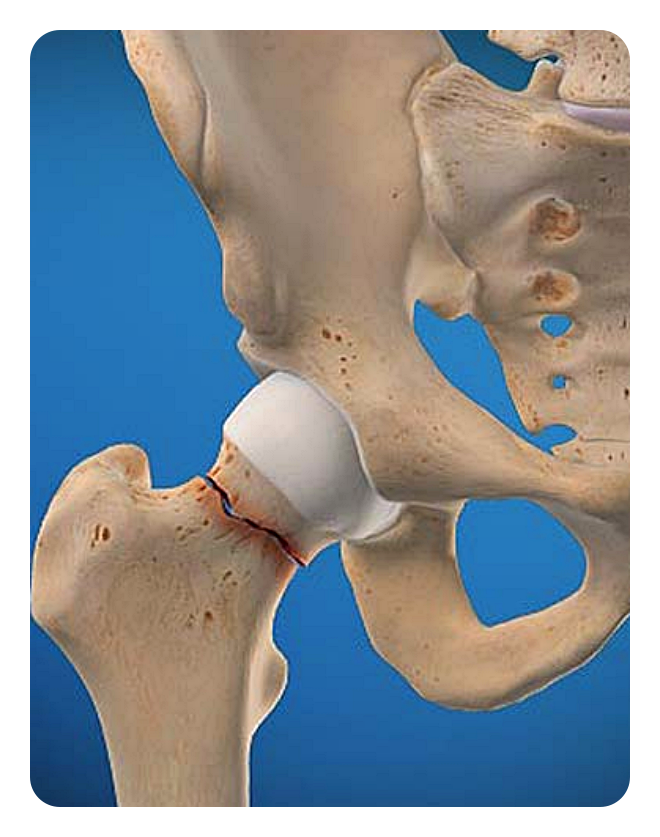

골절 고정술: 이 수술은 골절된 뼈를 원래 위치로 돌려놓고 고정하는 것으로, 골절된 부위가 제대로 회복되도록 돕습니다. 외부고정과 내부고정으로 나뉘어집니다.

고관절은 몸을 지탱하고 움직이는 데 중요한 역할을 하는데, 골반과 대퇴골을 연결하는 관절입니다. 우리의 일상적인 활동에서도 이 관절은 걷기나 뛰기와 같은 움직임뿐만 아니라 체중을 지탱하고 다리를 움직이는 데에 필수적입니다. 그러나 나이가 들거나 부상 등으로 고관절이 손상되면 통증과 움직임 제한과 같은 문제가 발생할 수 있습니다.